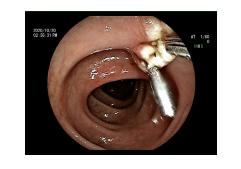

肠镜检查发现距离肛门50cm处结肠息肉

经肠镜特殊处理

行内镜下处理后病理情况

肠镜切除后病理多提示炎性息肉,或者轻和(或)中度异型,这些情况多还是良性病变,内镜下切除就可以了。但是对于内镜下处理不到或者提示早癌的,要行结直肠部分切除术或者结直肠癌根治性手术。